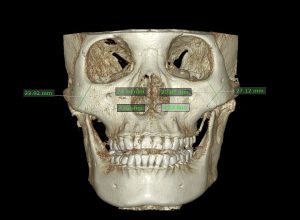

Trước tiên, người bệnh sẽ được bác sĩ thăm khám nhằm đánh giá tình trạng khuôn mặt bệnh nhân, toàn trạng sức khỏe. Sau đó, bệnh nhân sẽ được chụp phim khuôn mặt dưới các góc chụp khác nhau, chụp phim CT hàm mặt, X-quang xương sọ-hàm mặt.

Sau đó, dựa trên kết quả đo đạc trên phim CT và X-quang xương hàm mặt, kết hợp ảnh chụp và khám lâm sàng, bác sĩ sẽ trao đổi với bệnh nhân về tình trạng khuôn mặt , cách thức phẫu thuật để đạt được kết quả tối ưu.

Dựa trên kết quả đo đạc từ trước, bác sĩ sẽ sử dụng lưỡi cắt song song ( một loại lưỡi cắt được bác sĩ nghiên cứu và phát triển dựa trên quy trình kỹ thuật và đảm bảo tuyệt đối vô khuẩn) nhằm lấy ra một mảnh xương gò má nhỏ . Điều này giúp việc kết xương được thẳng và chính xác tuyệt đối. Sau đó, xương gò má-cung tiếp sẽ được đưa về vị trí mới.